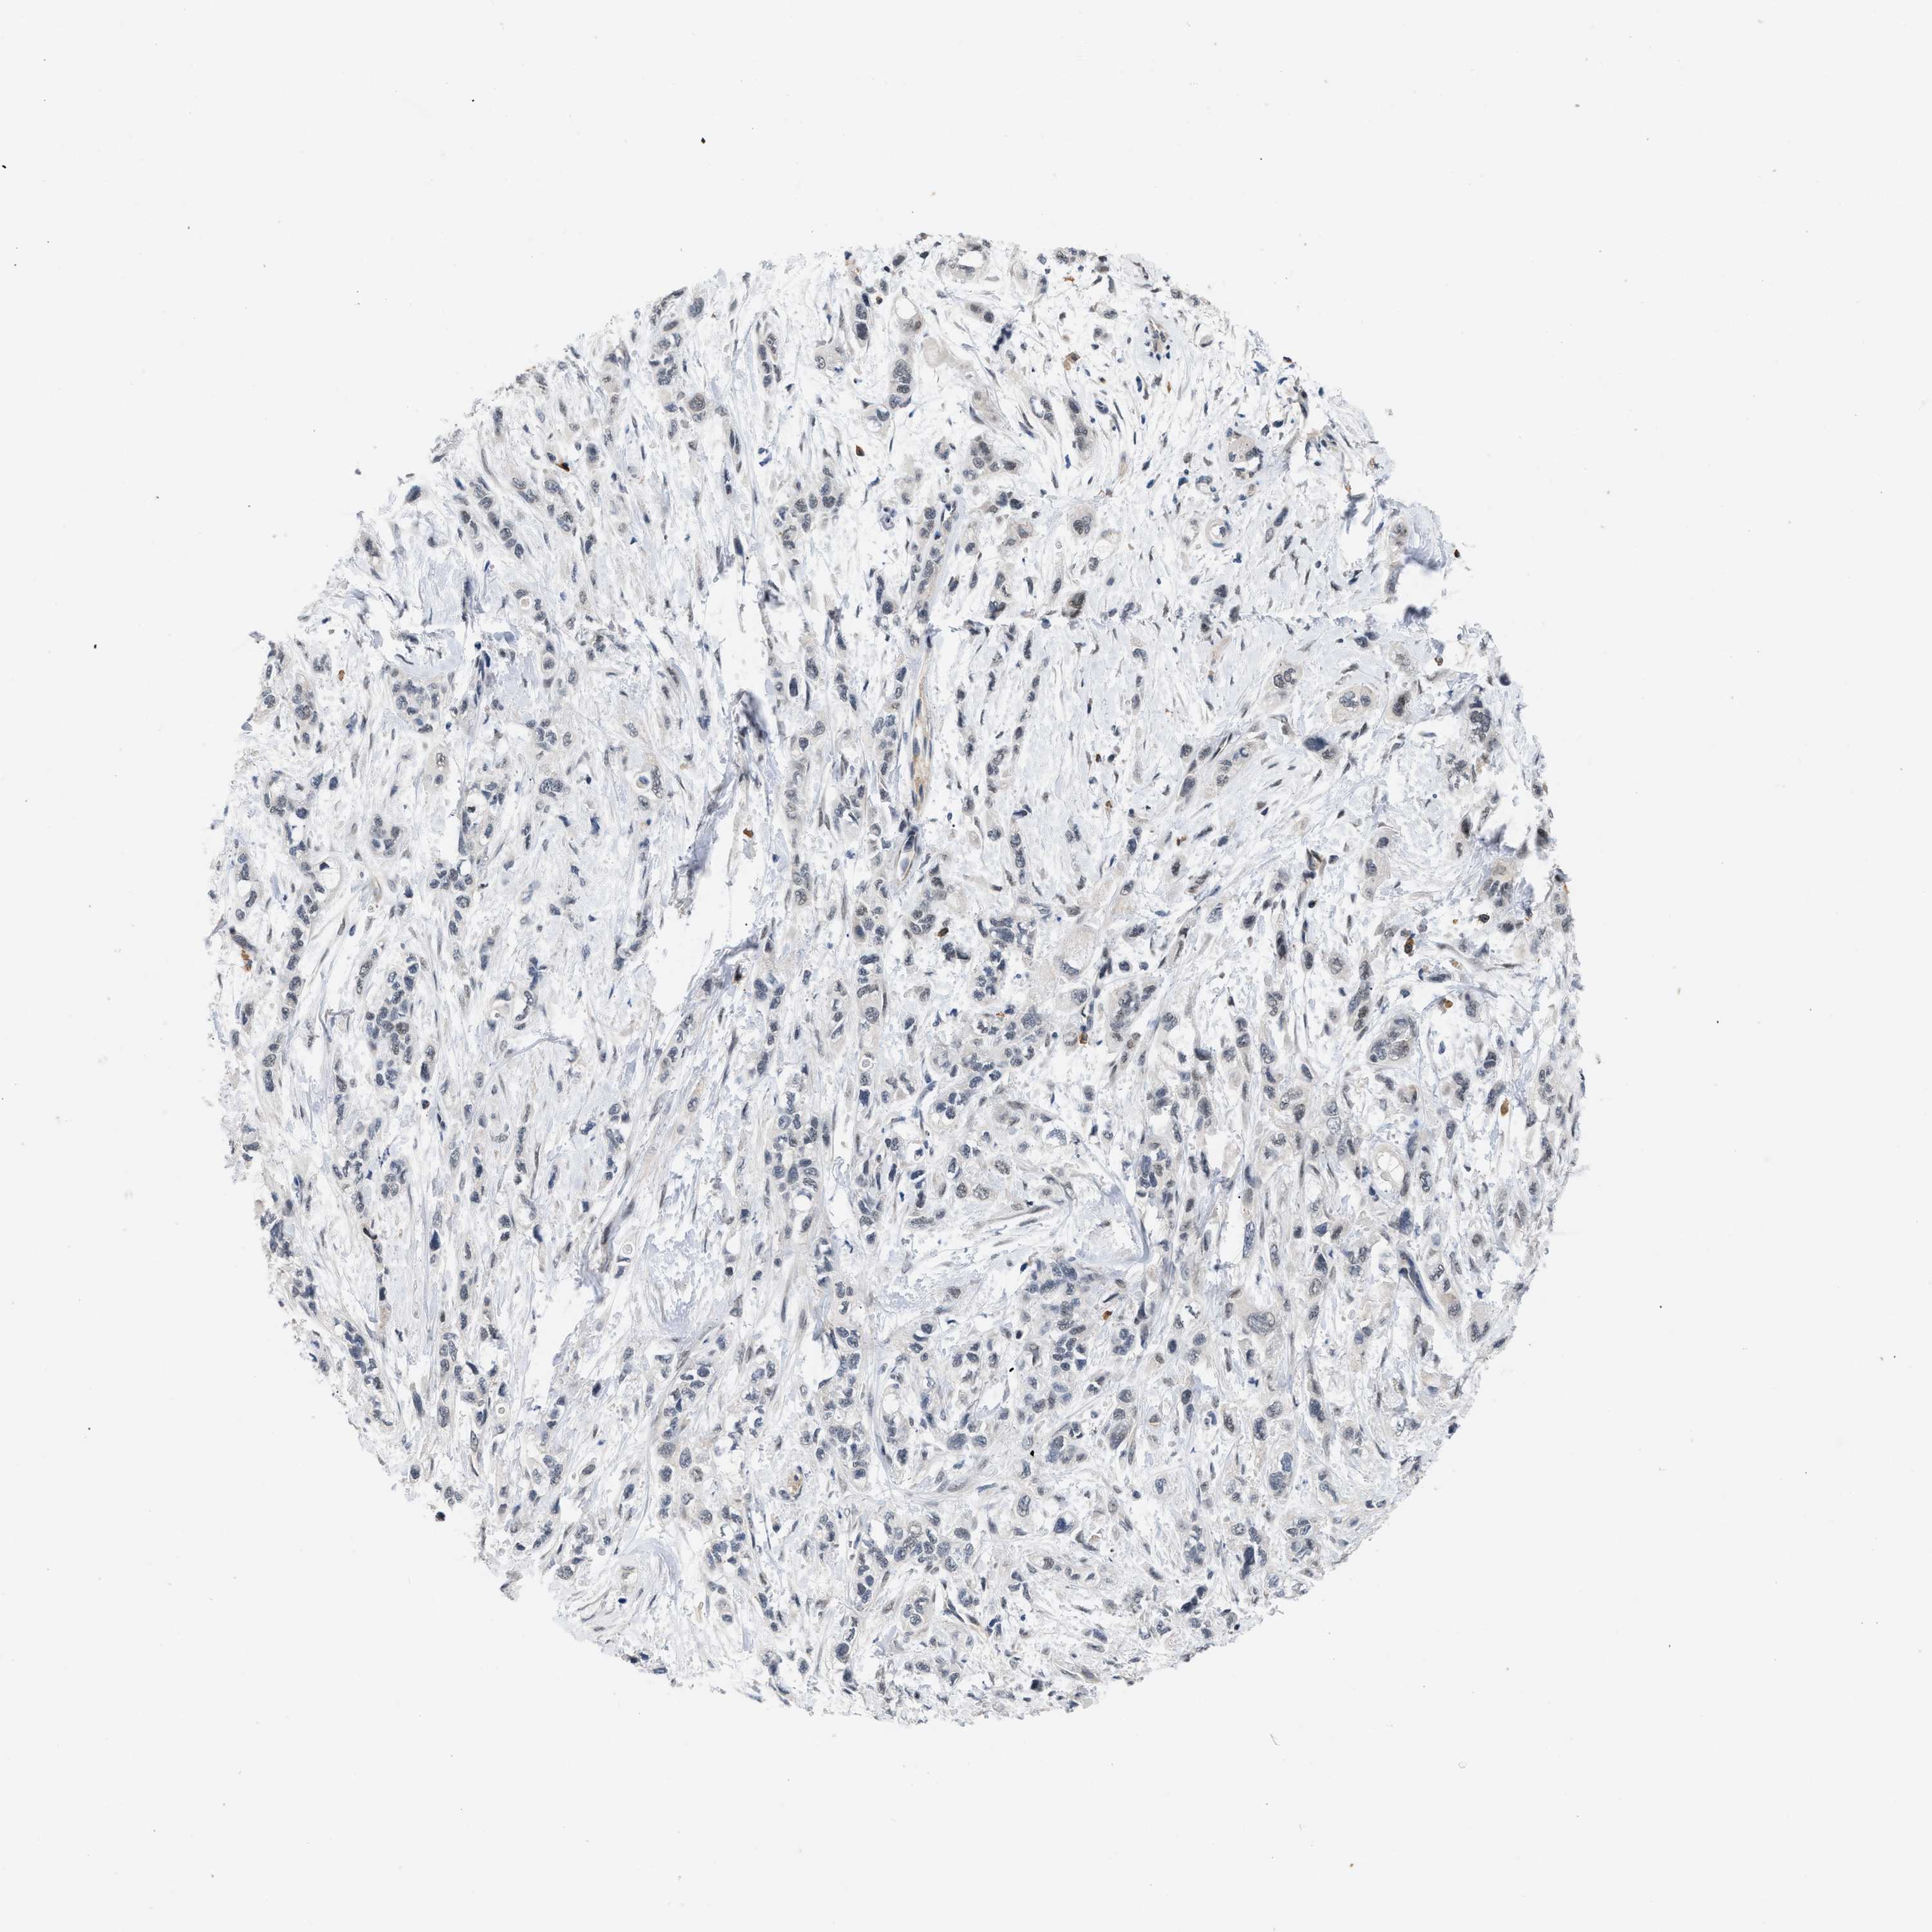

PANCREATIC CANCER - Protein expressioni

A mouse-over function shows sample information and annotation data. Click on an image to view it in a full screen mode. Samples can be filtered based on level of antibody staining by selecting one or several of the following categories: high, medium, low and not detected. The assay and annotation is described here.

Note that samples used for immunohistochemistry by the Human Protein Atlas do not correspond to samples in the TCGA dataset.

Antibody stainingi

Antibody staining in the annotated cell types in the current human tissue is reported as not detected, low, medium, or high, based on conventional immunohistochemistry profiling in selected tissues. This score is based on the combination of the staining intensity and fraction of stained cells.

Each image is clickable and will lead to virtual microscopy that enables deeper exploration of all samples and also displays staining intensity scores, fraction scores and subcellular localization as well as patient and tissue information for each sample.

Antibody CAB020802

Staining

High

Medium

Low

Not detected

Intensity

Strong

Moderate

Weak

Negative

Quantity

>75%

75%-25%

<25%

None

Location

Nuclear

Cytoplasmic/membranous

Cytoplasmic/membranous,nuclear

Adenocarcinoma, NOS